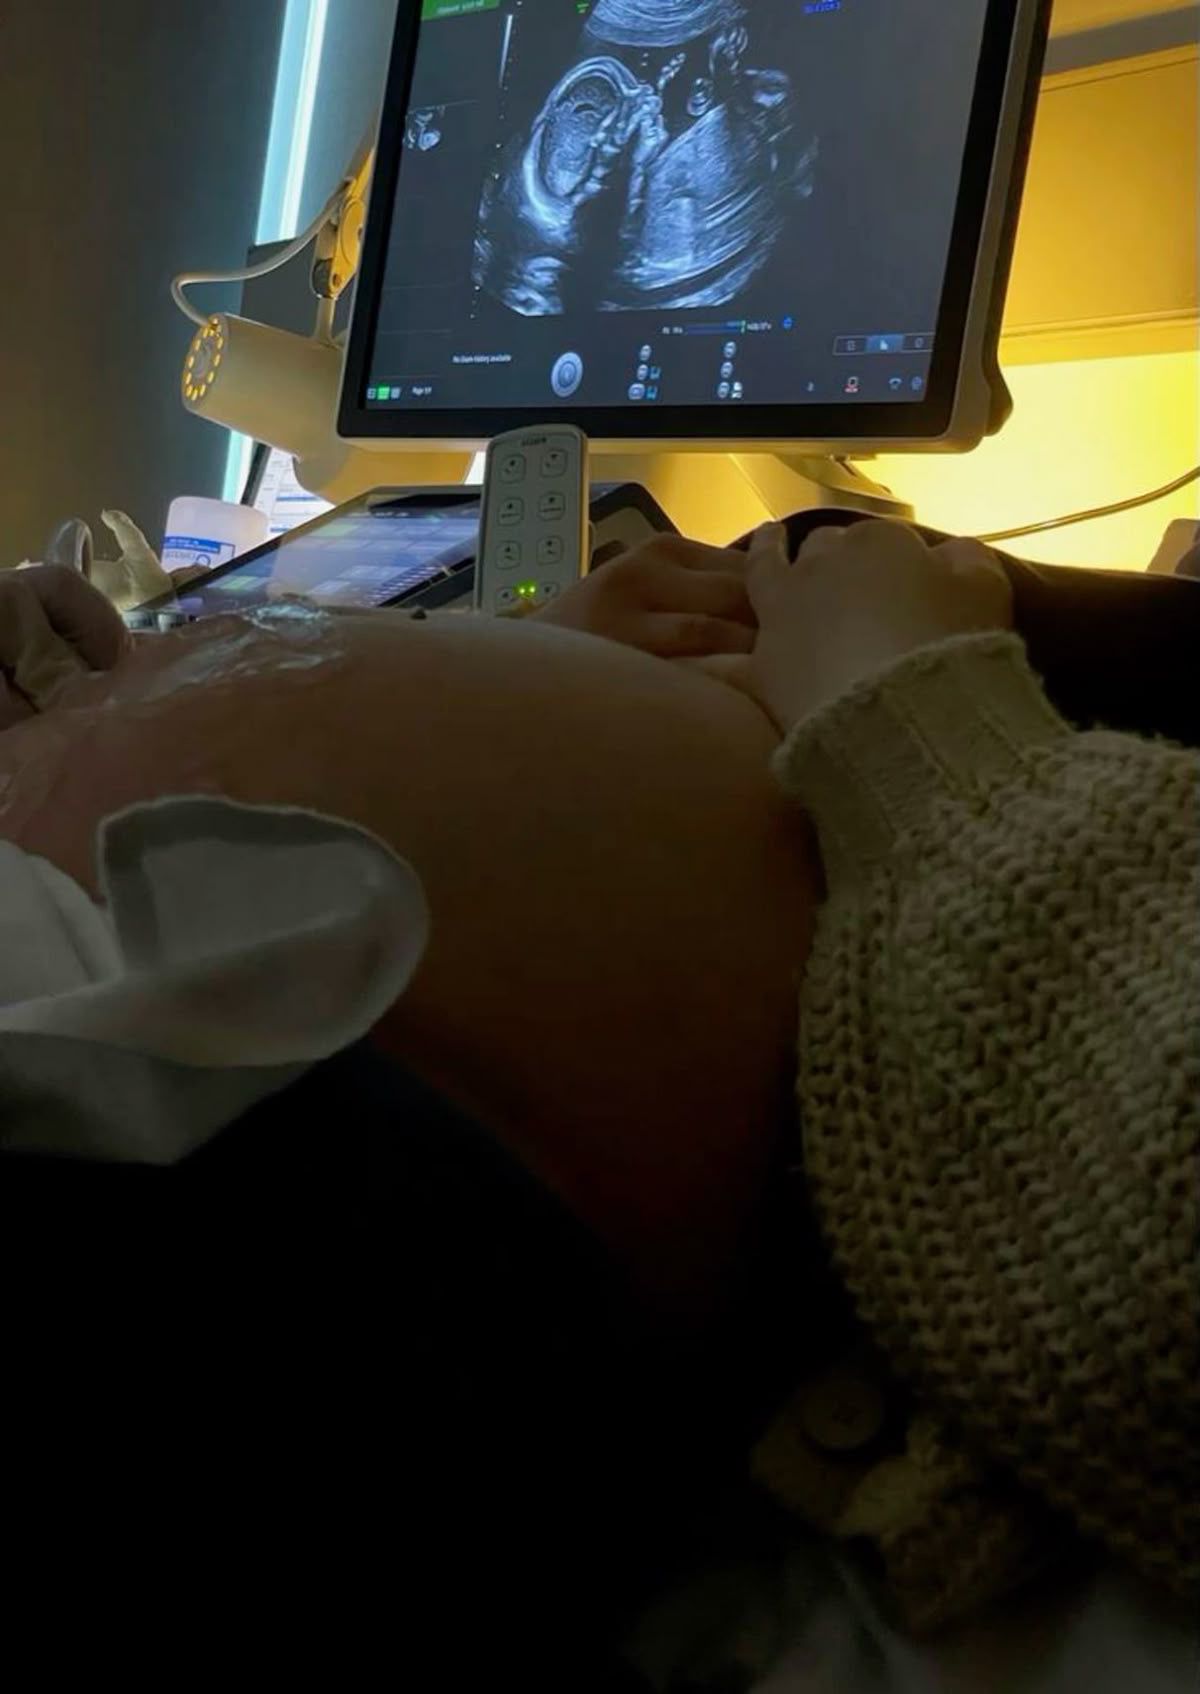

Ngày đi khám thai, em bé vẫn đang lớn dần từng ngày.